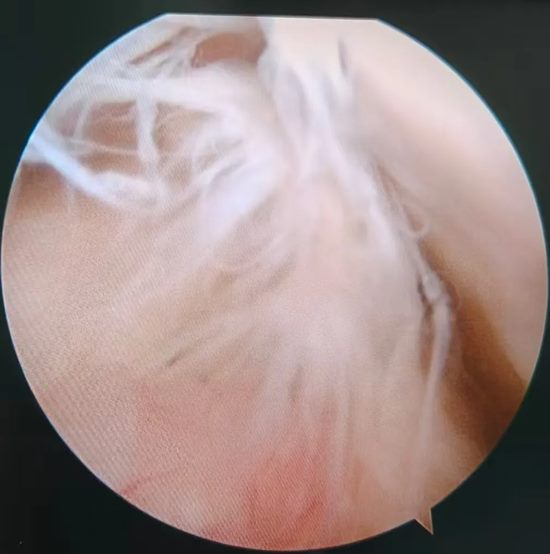

术中关节镜探查的断裂的前交叉韧带

"手术全程在关节镜直视下操作,视野清晰,能最大限度保护周围正常组织,出血少、感染风险低。"徐明杰主任介绍,术后结合个体化康复方案,患者第二天即可扶拐下地,预计数月后能逐步恢复运动能力,在康复医学科带领下,患者仅仅2-3天膝关节就可屈曲90度,这在自体肌腱重建交叉韧带上是不可能办到的。